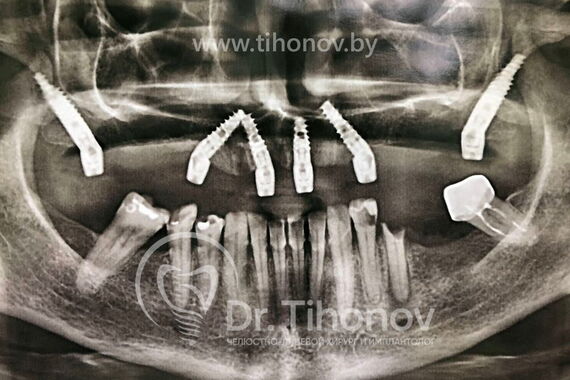

В процессе проведения операции на верхней челюсти были удалены оставшиеся разрушенные корни зубов, одномоментно установлены 6 имплантатов и на 5-й день зафиксирован в полости рта функциональный и эстетичный металлопластмассовый протез. Таким образом, удалось обойтись без дорогостоящих длительных процедур наращивания костной ткани и подарить пациентке красивую улыбку всего за 5 дней.